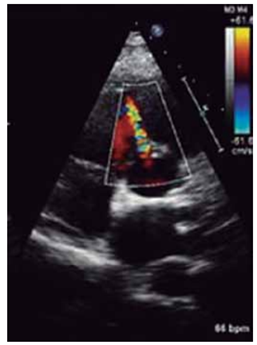

Criança, sexo masculino, 5 anos, realiza ecocardiograma para avaliação de sopro cardíaco.

(Arquivo pessoal; imagem utilizada com autorização)

A imagem indica: